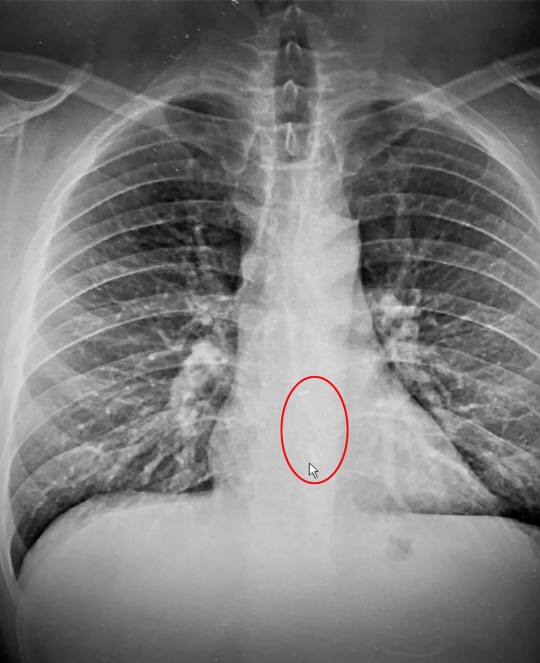

ഉറക്കത്തിൽ അറിയാതെ ഉള്ളിൽപ്പോയ എയർപോഡ് ഭാഗ്യവശാൽ ഗുരുതര പ്രശ്നങ്ങൾ ഒന്നും ഉണ്ടാക്കാത്ത തരത്തിൽ നെഞ്ചിനുള്ളിൽ തടഞ്ഞിരിക്കുന്ന നിലയിലായിരുന്നു

മസാച്യുസെറ്റ്സ് വോർസെസ്റ്റർ സ്വദേശിയാണ് ബ്രാഡ് ഗോത്തിയർ. എയർപോഡ് വിഴുങ്ങിക്കാണുമെന്ന തമാശ ഉയർന്നതോടെ ഉറക്കത്തിൽ അറിയാതെ വിഴുങ്ങിപ്പോയെന്ന ഭയം ബ്രാഡിനും ഉണ്ടായി. ആദ്യം ഒന്ന് മടിച്ചെങ്കിലും പിന്നീട് ആശുപത്രിയിലേക്ക് പോകാൻ തീരുമാനിക്കുകയായിരുന്നു. ഭക്ഷണം കഴിച്ച ബുദ്ധിമുട്ടാകും എന്നാണ് ആശുപത്രി ജീവനക്കാർ ആദ്യം സംശയം പ്രകടിപ്പിച്ചതെങ്കിലും എക്സ് റേ കണ്ടതോടെ കുടുംബത്തിന്റെ സംശയം സത്യമെന്ന് വ്യക്തമാവുകയായിരുന്നു.

ഉറക്കത്തിൽ അറിയാതെ ഉള്ളിൽപ്പോയ എയർപോഡ് ഭാഗ്യവശാൽ ഗുരുതര പ്രശ്നങ്ങൾ ഒന്നും ഉണ്ടാക്കാത്ത തരത്തിൽ നെഞ്ചിനുള്ളിൽ തടഞ്ഞിരിക്കുന്ന നിലയിലായിരുന്നു. എൻഡോസ്കോപ്പിയിലൂടെ അത് പുറത്തെടുക്കുകയും ചെയ്തു.